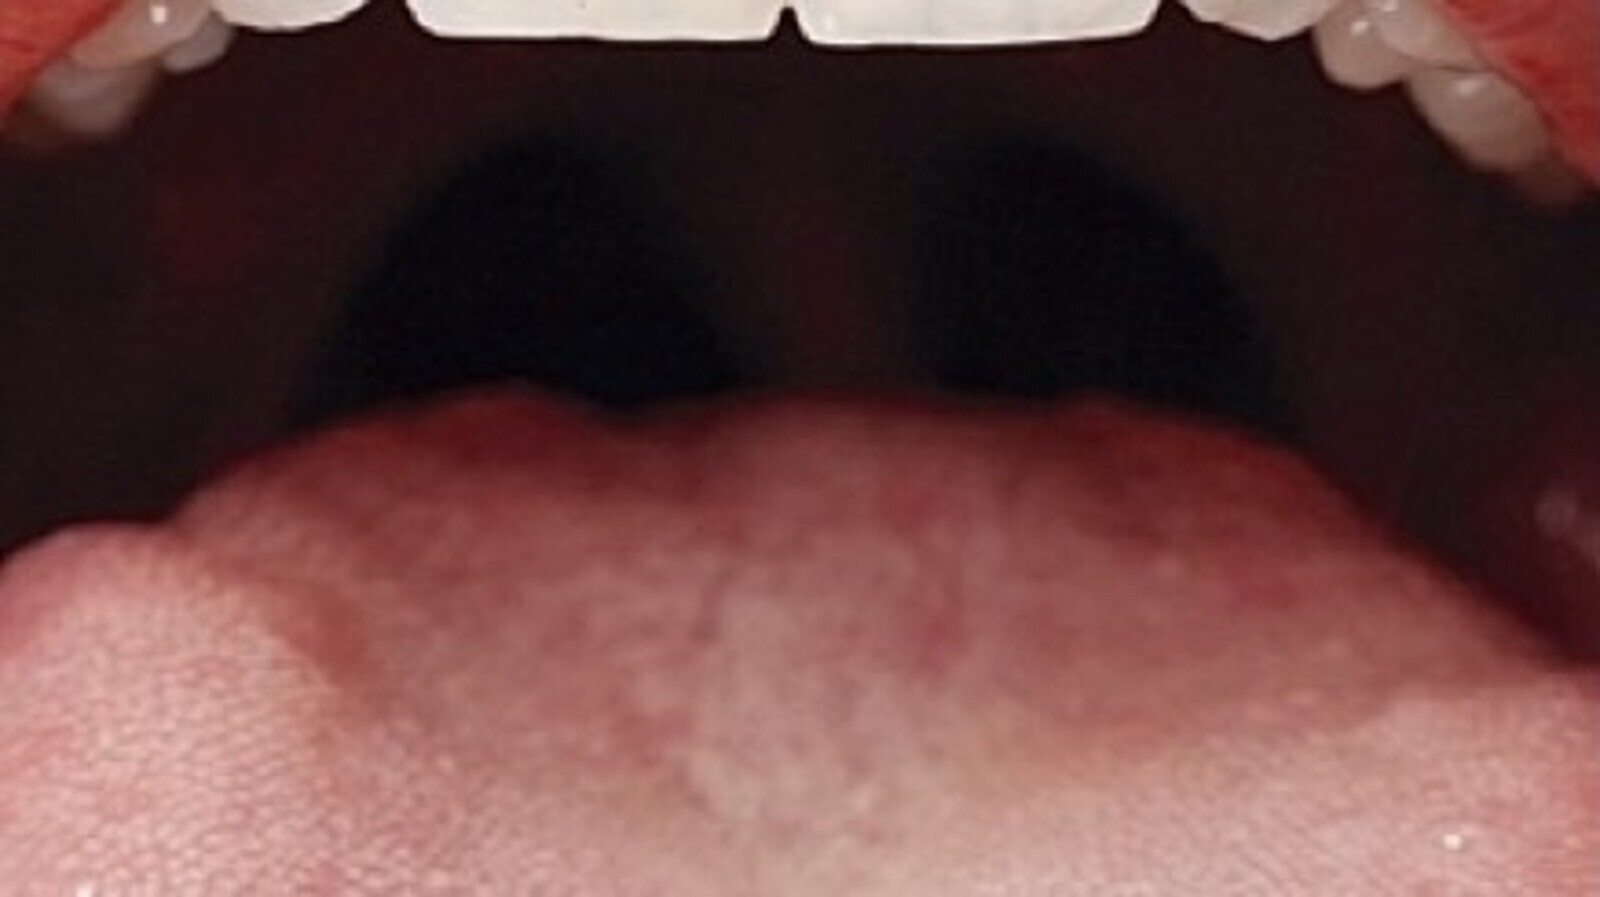

El dentista debe realizar una evaluación exhaustiva de toda la cavidad oral del paciente y, si detecta anomalías como úlceras, bultos, manchas rojas o blancas, puede recomendar pruebas adicionales, como una biopsia, para obtener un diagnóstico definitivo. Fotos: SECIB

Así, cuando un paciente acude a una revisión odontológica, el dentista debe realizar una evaluación exhaustiva de su cavidad oral que incluye las mejillas, los labios, la lengua, el paladar y las encías. Y si detecta anomalías como úlceras, bultos, manchas rojas o blancas, puede recomendar pruebas adicionales, como una biopsia, para obtener un diagnóstico definitivo.

En sus primeras etapas, el cáncer oral puede pasar desapercibido. Hay que prestar atención a los síntomas y signos de alarma, como una mancha de color blanco o rojo en la boca, o una pequeña úlcera que no se cura en unas dos semanas. Otros síntomas incluyen dolor o dificultad para tragar, hablar o masticar. El dolor de oído persistente en un solo lado también puede ser una señal de advertencia.